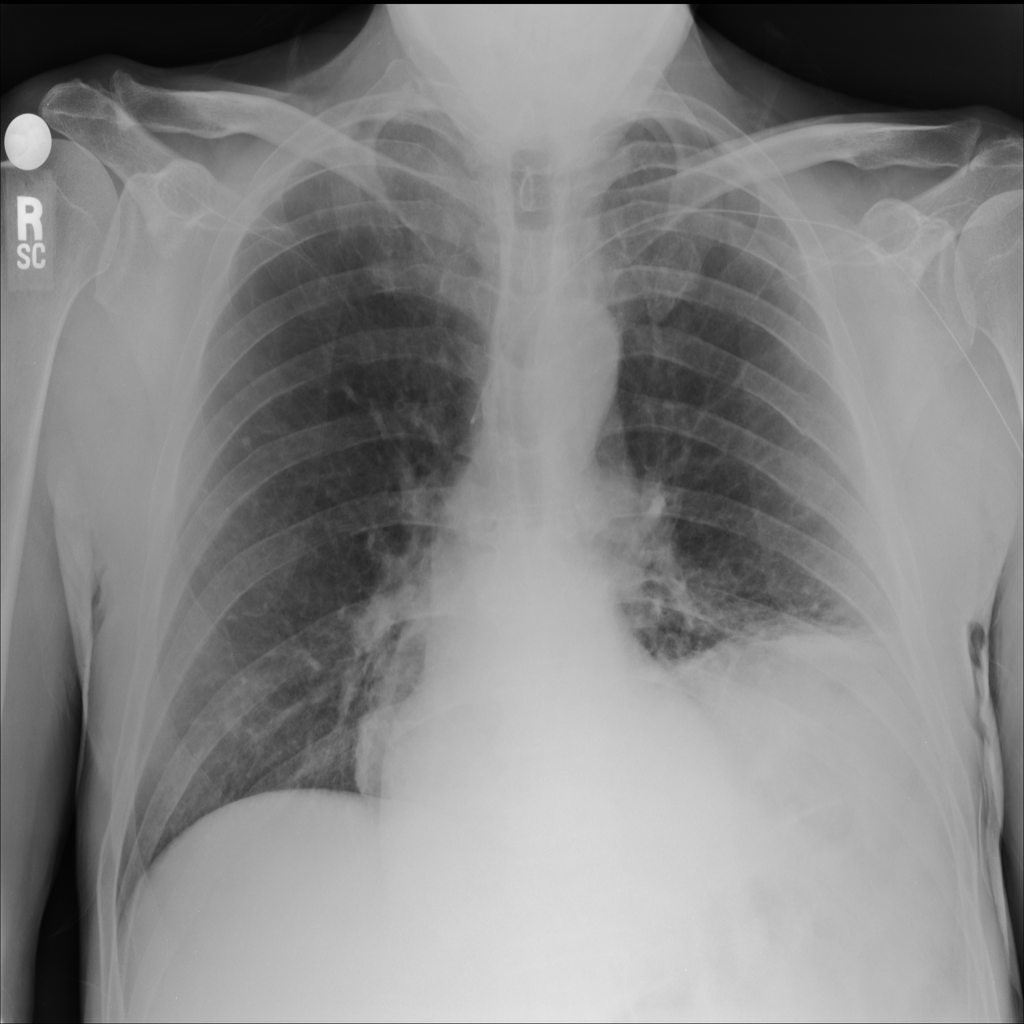

PAT-0ABD · IMG-000Hernia

PAT-0ABD · IMG-000

PA